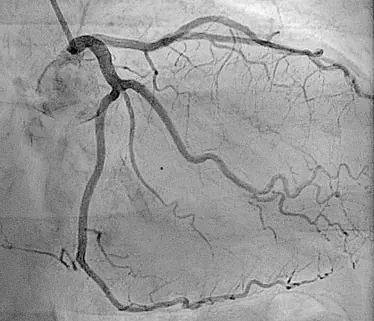

آنژیوگرافی کرونری

این نوع آنژیوگرافی برای بررسی عروق کرونری قلب استفاده می‌شود و به تشخیص بیماری‌های عروق کرونری مانند تنگی و انسداد عروق کمک می‌کند.

آنژیوگرافی به تشخیص بیماری‌های عروق کرونری مانند تنگی و انسداد عروق کرونری کمک می‌کند و اطلاعات دقیقی درباره وضعیت عروق قلب فراهم می‌کند.

این روش برای شناسایی تنگی و انسداد عروق خونی در نقاط مختلف بدن استفاده می‌شود و به پزشکان کمک می‌کند تا مشکلات را به طور دقیق تشخیص دهند.